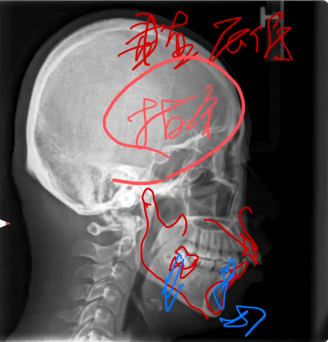

而高角深覆盖、低角深覆盖就是日常说的II类牙齿情况,对于高角的II类,垂直向压低是重点,对于低角的II类,后牙升高是重点,这是它们两个治疗的思路。

高角深覆盖由于下颌平面角较大,在正畸内收过程中要避免后牙伸长,以免加重高角面型。尤其后部咬合平面,更多的是磨牙垂直向的压低,同时下前牙的内收。

常采用种植支抗钉来压低后牙,施加适当的力量来压低磨牙,这可以有效控制垂直高度,为前牙内收创造稳定的基础。同时,要注意内收的方向,由于高角患者的颌骨特点,前牙内收应适当增加垂直向分力,以避免前牙过度唇倾。常见以拔牙方案为主,拔牙易降低垂直高度。